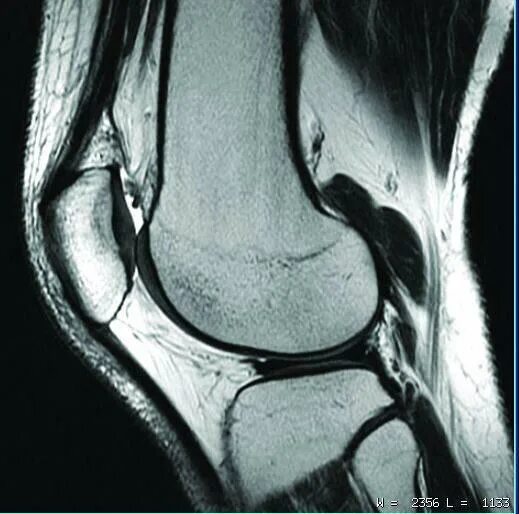

Мрт коленного сустава набережные